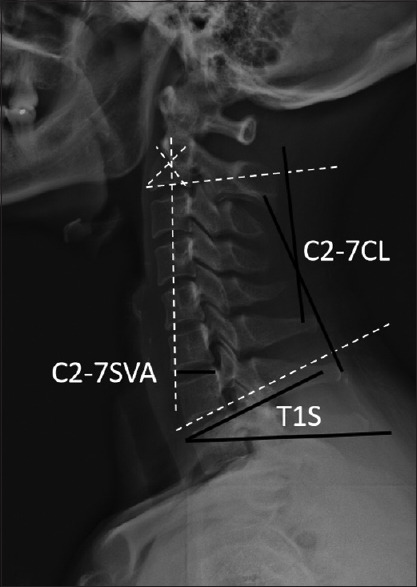

Materials and methods: Three hundred sixty-six patients diagnosed with CDD were enrolled from 2018 to 2023. Grouped based on T1S-CL, a value of T1S-CL <20° defined as a matching group, and a value of T1S-CL >20° comprised a matching group. All patients underwent only cervical anterior or posterior approach surgery. Clinical indexes of the Japanese Orthopedic Association (JOA) score, Visual Analog Scale (VAS) and neck disability index (NDI), and radiologic parameters of T1S, CL, and sagittal vertical axis (C2-7 SVA) were recorded and analyzed.

Results: Before surgery, there were significant differences in factors between the two groups for CL, T1S, and T1S-CL (P < 0.05). Postoperatively, clinical indexes and radiological parameters changed significantly (P < 0.001) in each group. There are significant correlations indicated between T1S and CL (P < 0.05) except for one in a mismatching group of posterior approach (P > 0.05) postoperatively. There are significant correlations indicated between T1S-CL and T1S, CL (P < 0.05) in two groups of anterior approaches except for posterior approaches (P > 0.05).